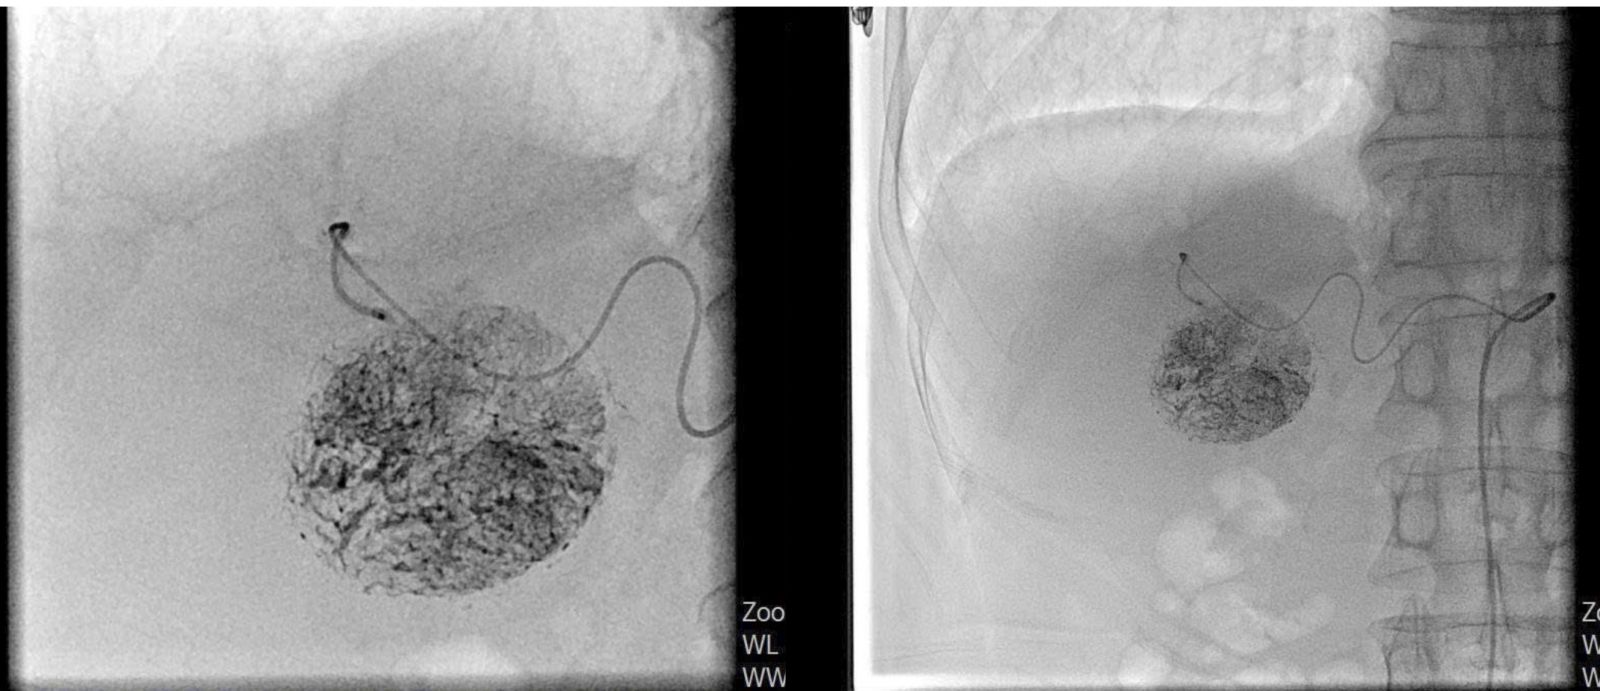

Hình ảnh khối u bắt thuốc tròn đều sau can thiệp.

Ca can thiệp được tiến hành thành công vào ngày 04/8. Hiện sức khỏe ông C. ổn định, sinh hoạt bình thường, dự kiến xuất viện vào ngày 9/9/2025. Chia sẻ niềm vui, ông nói: “Tôi biết Bệnh viện đã có nhiều ca UNG THƯ GAN điều trị bằng phương pháp TACE thành công nên rất tin tưởng. Giờ sức khỏe tôi dần hồi phục, cảm ơn bác sĩ đã tận tâm điều trị”.